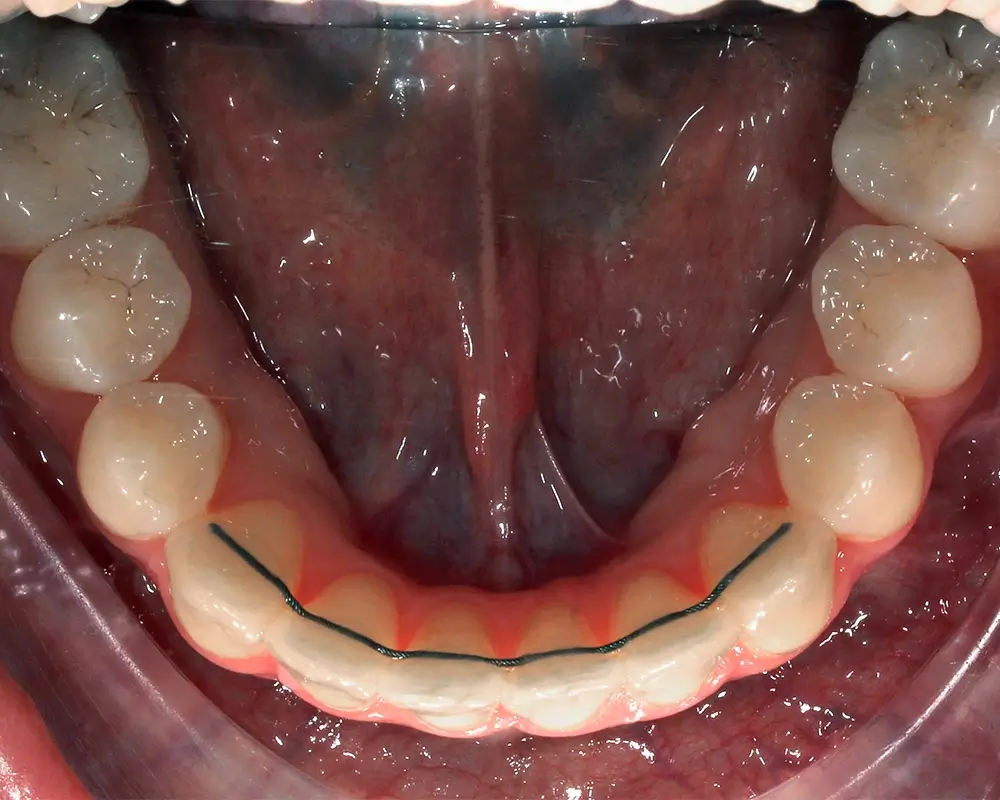

Открытый прикус - Кейс 6

Эффективность устранения дефекта прикуса посредством элайнеров FlexiLigner.

30

Количество кап НЧ

Количество кап ВЧ

Результаты лечения